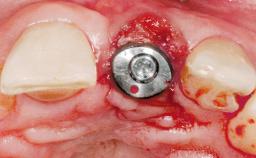

Type of Implants One-Piece

Attachment One-Piece

Loading Protocol Immediate

Retention Screw-retained Screw-retained

Provisional Implant-Supported Prosthesis Prosthodontic margin < 3 mm apical to mucosal margin Prosthodontic margin < 3 mm apical to mucosal margin